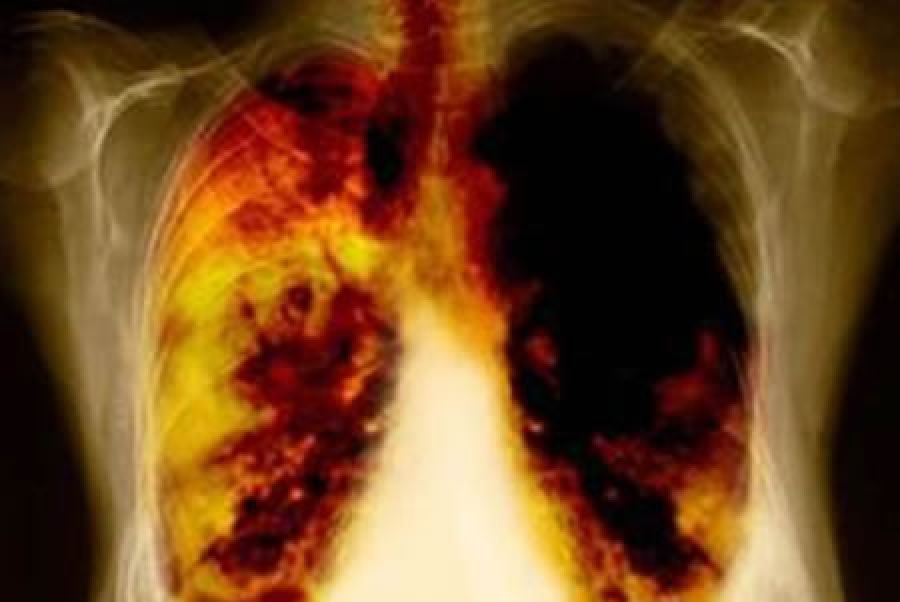

El 80% de los casos reciben un diagnóstico en etapas avanzadas, cuando el cáncer ya ha hecho metástasis y la tasa de supervivencia es del 4%. Esto se debe a que no se presentan síntomas hasta que la enfermedad se ha propagado. “El cáncer de pulmón es un tema que cobra gran relevancia al ser el más común en México y en el mundo y provocar más muertes, incluso por encima del cáncer de mama, colorrectal y próstata combinados”; aseguró el Dr. Jorge Arturo Alatorre, médico oncólogo del Instituto Nacional de Enfermedades Respiratorias Ismael Cosío Villegas (INER).

De acuerdo con el Dr. Alatorre, la mayoría de los cánceres de pulmón no causan ningún síntoma, sin embargo mencionó que entre los más frecuentes se encuentran la tos que no desaparece o que empeora, dolor en el pecho que a menudo empeora cuando se respira profundamente, tose o se ríe, ronquera, pérdida de peso y pérdida de apetito, tos con sangre o esputo (saliva o flema) del color del metal oxidado, dificultad respiratoria, cansancio o debilidad, infecciones como bronquitis y neumonía que no desaparecen o que siguen recurriendo y silbido de pecho.